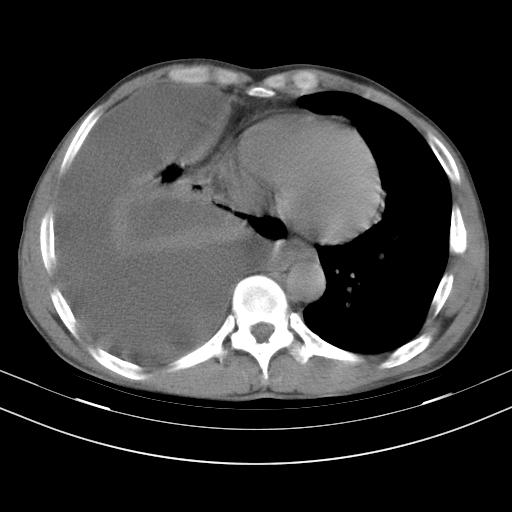

男性,44岁,结核病史多年。现胸闷气短,咳嗽,偶咳血。

右侧胸腔积液

右肺下叶不张

双肺多发结节影最分空洞形成考虑占位不除外结核

双肺陈旧性病变

1、右侧大量胸腔积液伴右肺压缩性膨胀不全,建议抽液治疗后复查 2、两肺继发性tb伴空洞形成。

1)两肺继发性肺结核伴空洞形成,左肺多发性结核球。2)右侧大量胸腔积液伴右肺部分膨胀不全。3)纵隔淋巴结肿大。